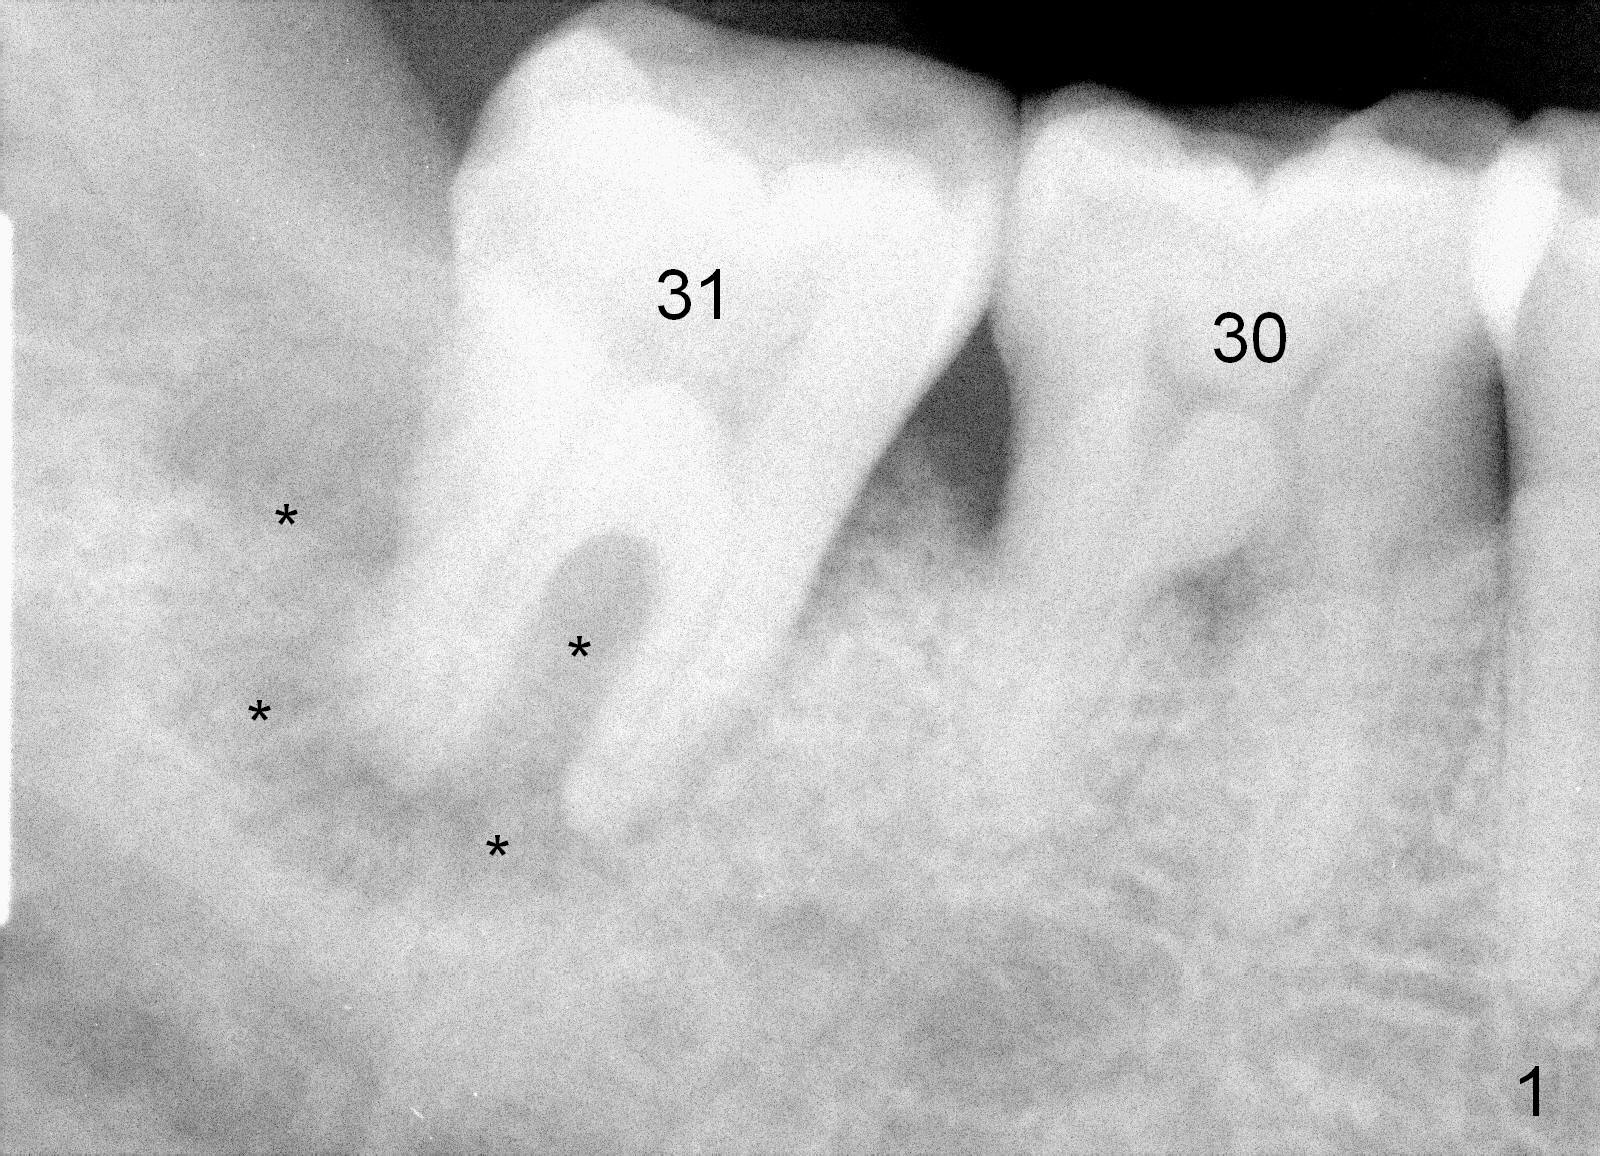

One year and a half years ago, the tooth #31 of a 48-year-old man had infection (Fig.1 *) and was extracted without implant.  There was more bone loss in the distal of #30 than in the mesial (Fig.2 *).  Recently the patient returns with infection at #30 distally with severe bone loss (Fig.3 *).  An immediate implant is to be placed mainly in the mesial socket (Fig.4 (bone-level), Fig.5 (tissue-level)).